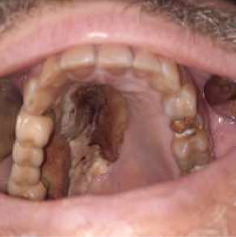

简介:毛霉病是一种罕见但严重的感染引起的真菌称为毛霉菌。它是一种危及生命的、高度侵袭性的血管侵入性感染,主要影响免疫功能低下的人群。方法和结果:2021年至2023年初,在塞尔维亚贝尔格莱德大学口腔医学院颌面外科诊所(“诊所”),医疗小组(“小组”)治疗了5名患有鼻-眶-脑型毛霉菌病的患者。在发现毛霉病之前,所有5名患者最近都已从COVID-19感染中康复。他们都在新冠肺炎专科医院度过了相当长的时间(平均住院1个月)。该小组根据2019冠状病毒病大流行时的毛霉病筛查诊断和管理指南(2019冠状病毒病患者指南/印度医学研究委员会,2021年5月出版,经世卫组织批准)对这些患者进行了治疗。治疗包括几个阶段,其中小组负责并开展早期诊断和手术干预阶段,而其他诊所的同事则协助进行毛霉病的其他治疗/管理阶段。结论:本文的目的是提出5例诊断为毛霉病的患者,特别关注两例因其病情接受手术干预作为抗真菌治疗的一部分的患者。

Introduction: Mucormycosis is a rare but serious infection caused by fungi called mucormycetes. It is life-threatening, highly aggressive angioinvasive infection, which mainly affects immunocompromised people. Methods and Results: During 2021-early 2023, at the Clinic for Maxillofacial Surgery, Faculty of Dental Medicine, University of Belgrade, Serbia (the "Clinic"), medical team (the "Team") treated five patients, with a rhino-orbital-cerebral form of mucormycosis. All five patients had recently recovered from COVID-19 infection prior to detection of mucormycosis. All of them spent a considerable amount of time (on average 1 month of hospitalization) at COVID-19 specialized hospitals. The Team treated these patients following the guidelines for screening diagnosis and management of mucormycosis at the time of the COVID-19 pandemic (COVID-19 patient guidelines/Indian Council of Medical Research, published in May 2021 approved by WHO). Treatment included several phases, out of which the Team was responsible for and carried out early diagnosis and surgical intervention phase, while colleagues from other clinics assisted in other phases of treatment/management of mucormycosis. Conclusion: The goal of this paper is to present five patients diagnosed with mucormycosis, with a special focus on two patients who, due to their condition, received surgical intervention as part of their antifungal treatment.